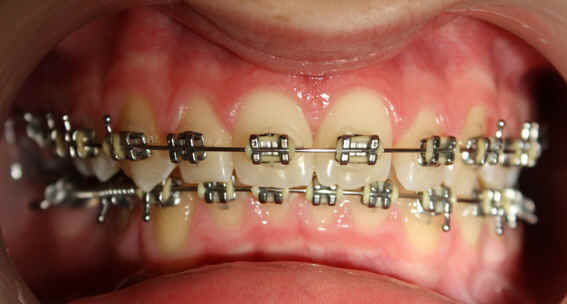

Malpositioned Premolar 13 year-old Caucasian boy

Pre-op 2009/04/18